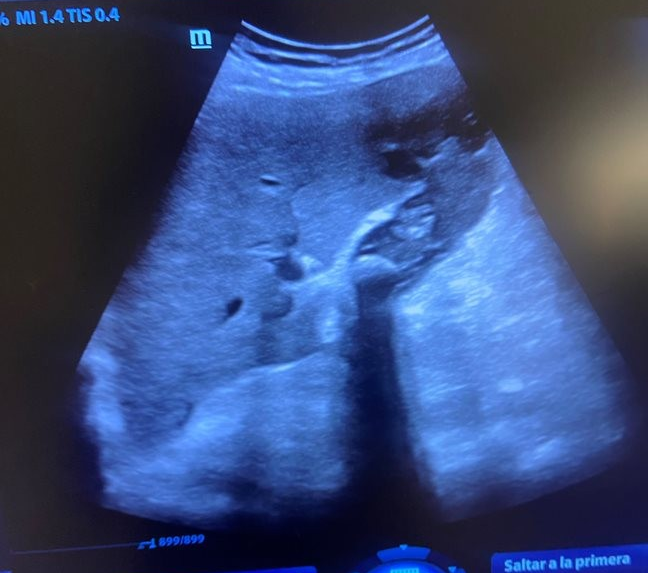

Paciente 1: vesícula con paredes muy engrosada, con contenido en su interior y empastamiento sugerente de abscesificación, derivada a urgencias y diagnóstico de colecistitis flemonosa.